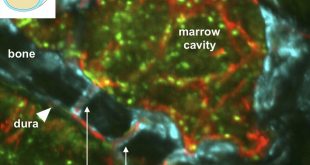

ادامهی نوشتهکشف تونل مخفی در مغز انسان

نوروسافاری | محققان دانشگاه “هاروارد” دریافتند که در مغز ما تونلهای کوچکی وجود دارد که سبب انتقال جریان خون به مغز میشوند. دانشمندان اخیرا دریافتهاند که در سر انسانها تونلهای مخفی کوچکی وجود دارد که جمجمه را به مغز متصل میکند. اینگونه به نظر میرسد که این کانالها به سلولهای …